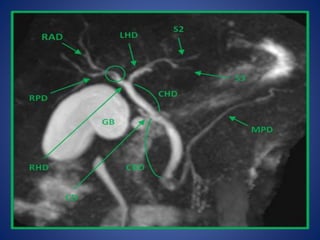

Bile Ducts Intrahepatic Ducts Theliver is divided into right and left lobes on the basis of portal vein anatomy and biliary drainage. The right lobe is divided into anterior and posterior segments, and the left lobe is divided into medial and lateral segments by the fissure of the ligamentum teres. Small branching interlobar bile ducts merge into larger ducts until the major left and right hepatic ducts are formed. A left medial segment duct and a left lateral segment duct normally join to form the main left hepatic duct.

• 33.

The left lateralsection is divided into superior (segment II) and inferior(segment III) segments. Union of ducts of segment II and III behind the umbilical part of left portal vein form the left hepatic duct (LHD) which then receives the duct from segment IV. Average length of the LHD is 1.7 cm and diameter is 3.0 mm (1.08). The right hepatic duct branches near its take off from the CHD. In approximately 60% of patients, the right hepatic duct has a dorsocaudal branch, with a characteristic hook-like configuration proximally, draining the posterior segment of the right lobe, and a ventrocranial branch, draining the anterior segment of the right lobe. The right anterior sectoral duct (RASD) drains segments V and VIII and the right posterior sectoral duct (RPSD) drains segments VI and VII. The RPSD passes horizontally and generally curves round the RASD to join its medial side to form the right hepatic duct (RHD). Average length of RHD is 0.9 cm and diameter is 2.6 mm.

• 37.

The bile ductsgenerally follow the internal hepatic segmental anatomy; however, marked variation in the branching pattern is common. Anomalies of the biliary system are found in 2.4% of autopsies, 28% of surgical dissections, and 5% to 13% of operative cholangiograms.